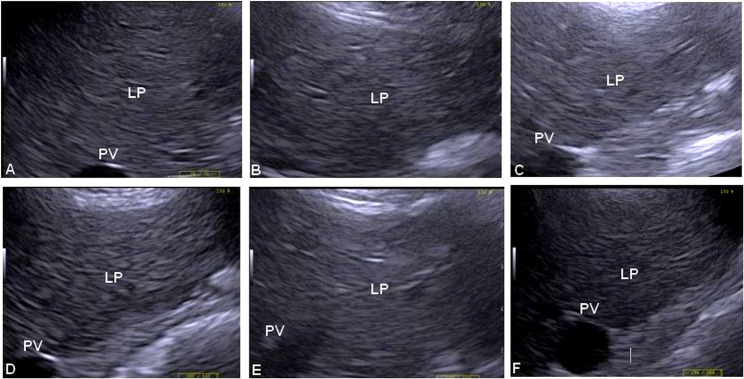

Results: On six occasions, the following were evaluated: body weight (BW), body condition score (BCS), ultrasound subcutaneous CFT, ultrasound gluteal muscle thickness, liver ultrasonography, and blood metabolites. The ultrasound CFT was significantly reduced at 4 days of fasting (P < 0.05). Donkeys with ≥ 7 mm of CFT before fasting were 6 times more likely to develop hyperlipidemia post-fasting (P < 0.01). Hepatic ultrasonography showed no hepatomegaly. Decrements of the portal vein (PV) diameter were noticed during fasting. The hepatic relative echogenicity (RE) significantly increased after 4 days of fasting, and then decreased after fasting (P < 0.05). The RE of ≥ 78 is a critical threshold for diagnosing hyperlipidemia (P < 0.001). The serum concentrations of triglycerides, total cholesterol, very low-density lipoproteins, high-density lipoproteins, and low-density lipoproteins peaked at 4 days of fasting (P < 0.05). The serum concentrations of FFA increased during fasting (P < 0.05) and then dropped after fasting.